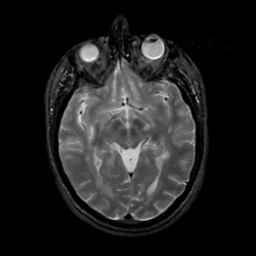

MR Study #6, March 17, 1991 -- Slice #22